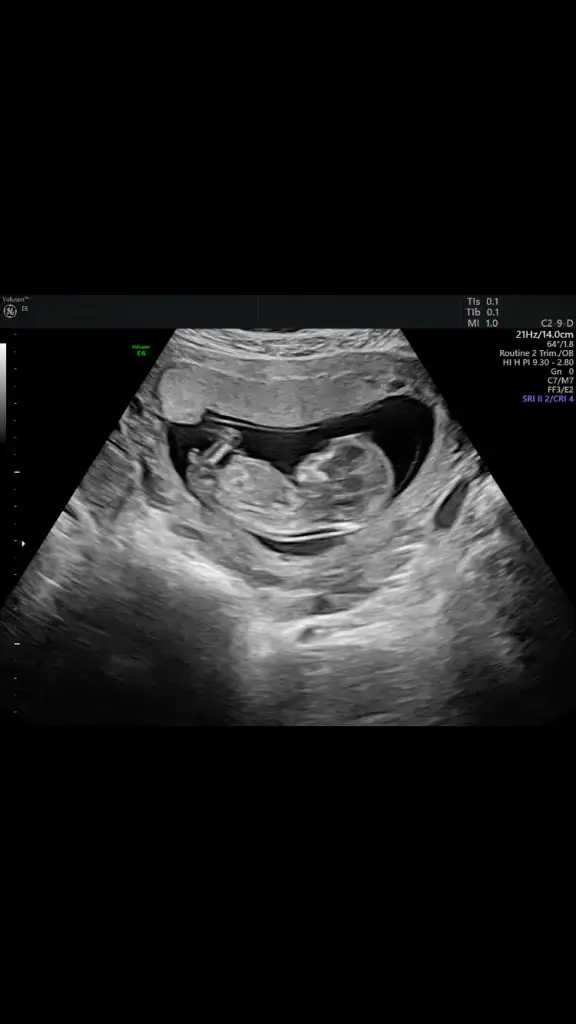

Bence de erkeğe benziyor Rabbim gönlündekini nasip etsin inşallah benimde 1 kızım var bnde erkek istiyorum o duyguyu çok merak ediyorum ama tabiki eli ayağı düzgün sağlıklı evlatlar nasip etsin RabbimKızlar merhaba ben yeniyim benide ekleyin grubunuza 5yaşında bir kızım var şükür şimdi ikinci gebeliğim 13haftalık olduk, geçen hafta kontrolüm vardı doktorum 16da cinsiyet söylüyorum öncesi yorum yapmıyorum dedi bana bir ay beklemesi kaldı bende ikra meyraya sordum 12+4 usg fotomuzla ikra erkek gibi dedi küçük bir çıkıntı var dedi, insan olmayanı istiyor tabi ikisinide tatmak için ama öncelik sağlık hayırlı evlat olsun, sizler gibi beklemedeyim bendesizede atayım usg bizi yorumlarınızı bekliyorum

Küçük bir çıkıntı mıKızlar merhaba ben yeniyim benide ekleyin grubunuza 5yaşında bir kızım var şükür şimdi ikinci gebeliğim 13haftalık olduk, geçen hafta kontrolüm vardı doktorum 16da cinsiyet söylüyorum öncesi yorum yapmıyorum dedi bana bir ay beklemesi kaldı bende ikra meyraya sordum 12+4 usg fotomuzla ikra erkek gibi dedi küçük bir çıkıntı var dedi, insan olmayanı istiyor tabi ikisinide tatmak için ama öncelik sağlık hayırlı evlat olsun, sizler gibi beklemedeyim bende ☺☺☺ sizede atayım usg bizi yorumlarınızı bekliyorum